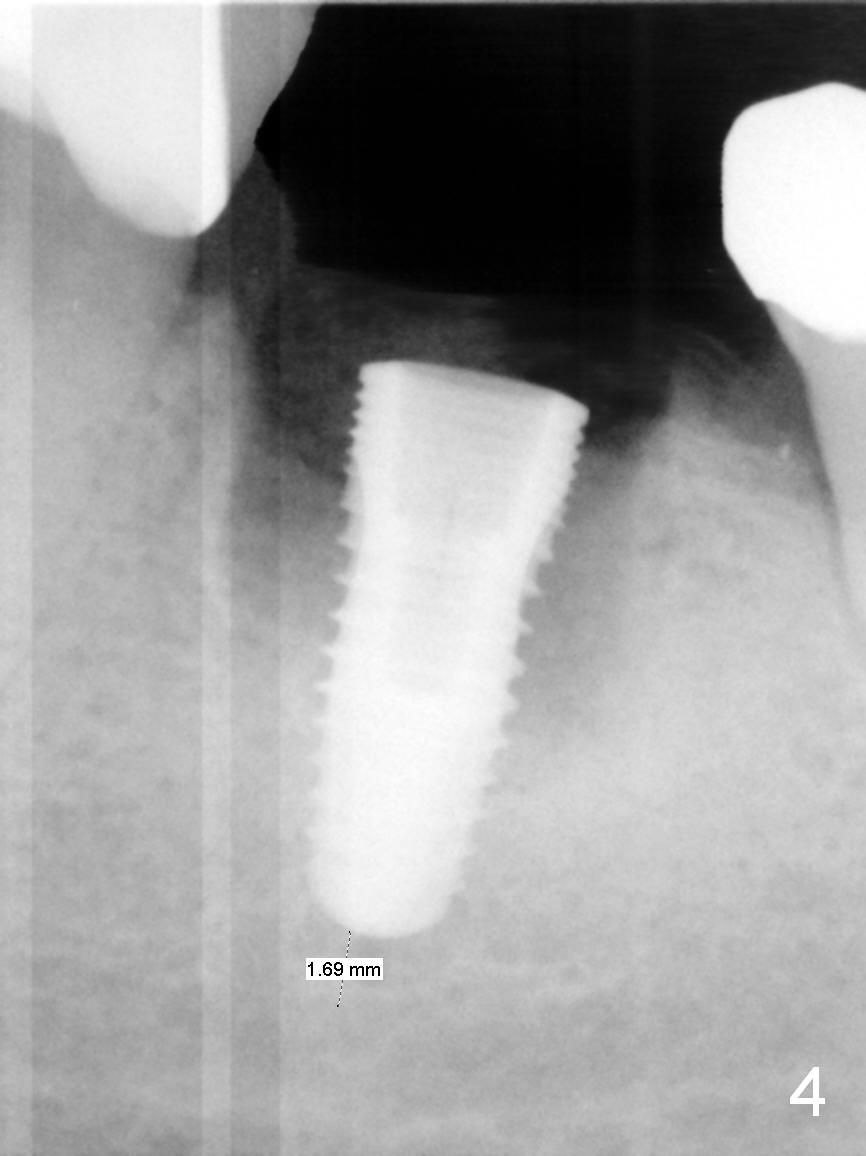

In fact, the buccal plate and the septum are defective. Osteotomy is initiated lingual to the center of the common sockets (Fig.1); depth is about 4 mm. When a 5x12 mm bone-level implant is placed (Fig.4), there is a gap mesiobuccally, which is later filled with bone graft (Fig.5 *). A large abutment (7.8x4(3) mm) is placed immediately (Fig.5 A) for an immediate provisional to close the sockets. The buccal abutment margin is ~ 1 mm subgingival, whereas the lingual ~2 mm supragingival. The abutment may need to be changed in the restorative phase (Fig.9,10).